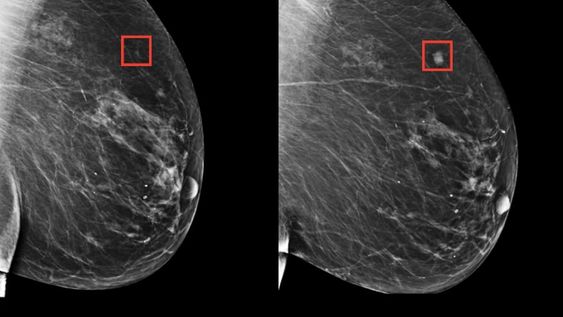

Se trata de una serie de algoritmos que aprenden los sutiles patrones del tejido mamario que son precursores de un tumor maligno. Foto: Massachusetts General Hospital.

El increíble descubrimiento que permite detectar cáncer de mama hasta 5 años antes gracias a la inteligencia artificial